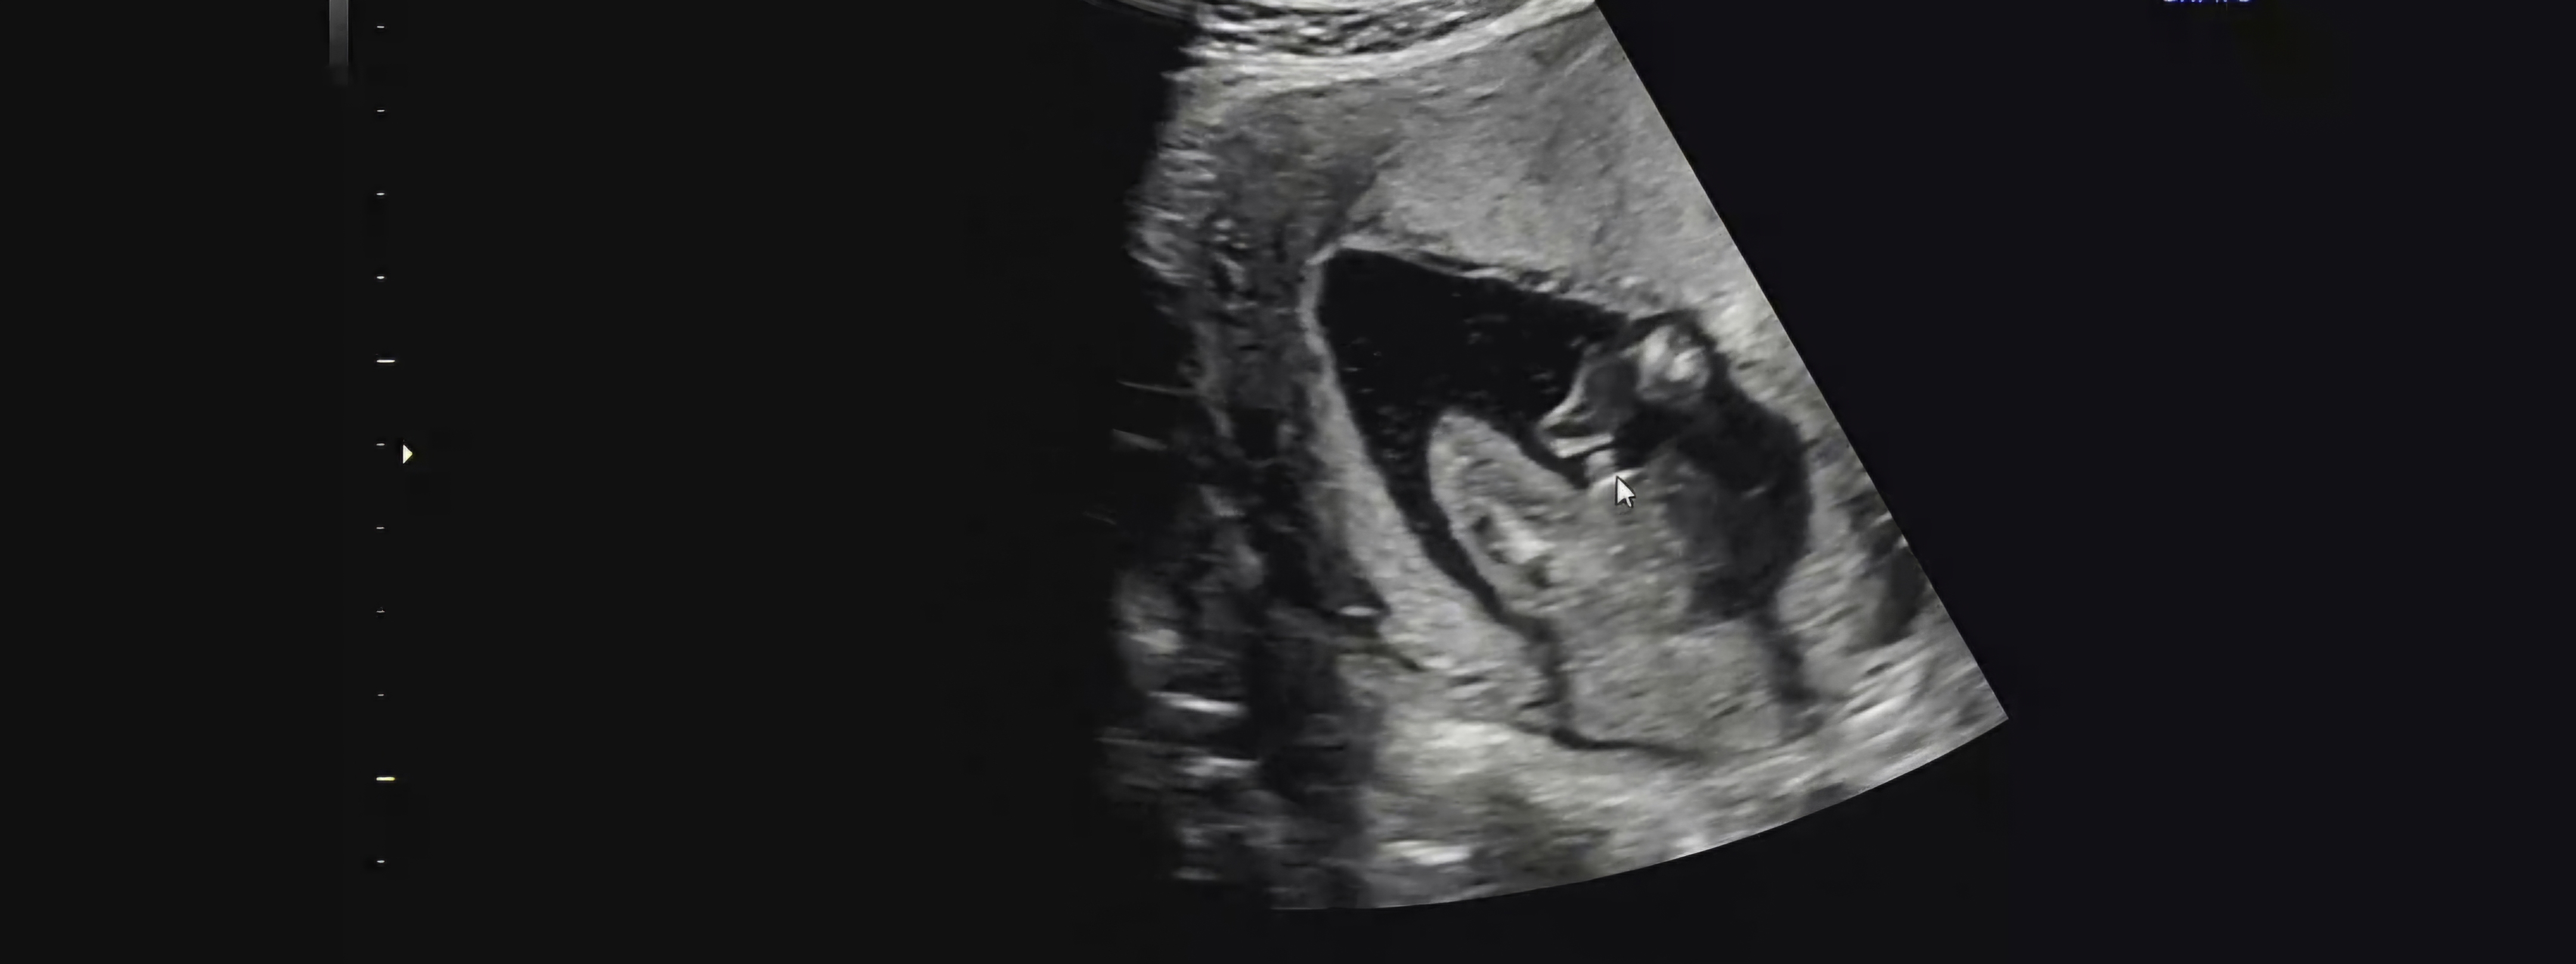

Y염색체 나왔거든요..? 근데 오류있는 경우도 있다고 들어서요. 16주 4일차 초음파인데 좀 성기부분이 떠있는 것 같아서 탯줄아닌가 싶어서요 어떻게 생각하세요??